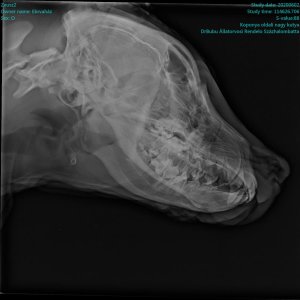

Ő Zeusz néven egy idős embernél élte napjait – csak 7 hónapos lett – és, hogy ne mérgezzék meg a szomszédok, vagy az éppen arra járó kisebbségiek, hát emberünk mindig magával vitte, mindenhová. Egy napon aztán, szerencsétlenség történt: „gazdi”-ra valaki ráhúzta a kormányt, a bicikli felborult, Zeusz leesett ( kedves „gazdi” a vázon szállította ) és az autó elütötte. Koponyatörés. „Gazdi” megúszta. Zeusz most nálunk gyógyul. Dr. Tóth Klára és kollégái mindent megtettek, hogy a kutyus túlélje az agyvérzést – feltételezett gyulladást, ami a koponyatöréssel járt. Most éppen annak örülünk, hogy Herkules – így neveztük el a kis harcost – már nem hány, hanem jó étvággyal eszik – sokszor, keveset szabad adnunk neki…..

Zeuszban nem volt chip és oltásai sem voltak. Most küzd, mint egy igazi kis Herkules.